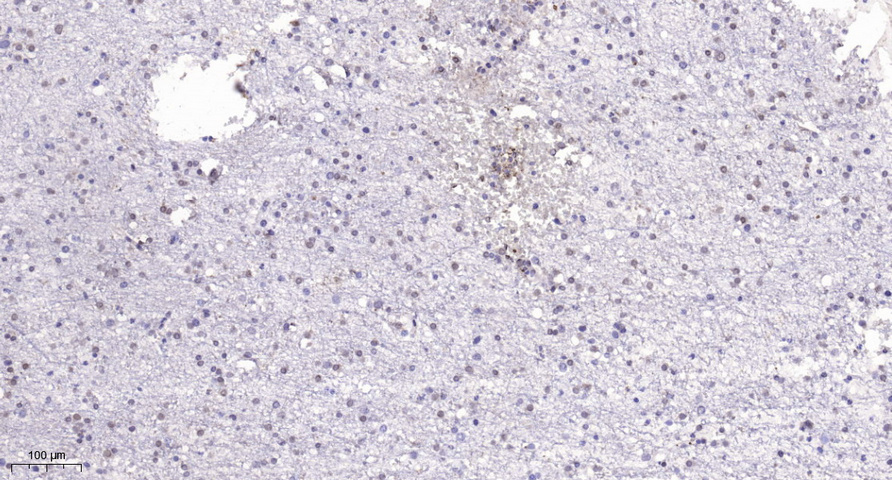

| Immunohistochemistry |

Immunohistochemical analysis of para?n-embedded human brain